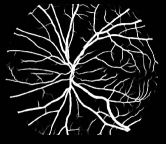

As pointed out in recent works [15, 17], a good semantic segmentation network should learn multi-level features. Further, it should have multiple stages with different receptive fields to learn more inherent features from different scales. FCN, taken as an example, uses skip connections to fuse multiple stages outputs, as well as the HED network, in which a series of side-output layers are added after each stage in VGGNet. The HED network was first proposed for edge detection, and further used for image-level vessel segmentation in recent studies [6, 16], with significant performance. However, our experimental results show that such network architecture is not appropriate for vessel segmentation directly. Figure 1 provides such an illustration. Reasons for this phenomenon are straightforward. On one hand, the side-output of the first layer often contains too many noises. On the other hand, the features produced by the last side-output layer are too coarse due to information loss of pooling operation. Obviously, the inaccurate vessel map of side-output1 and side-output4 should have negative impacts on the final segmentation result.

2.2 Bottom-top short connections

With the deepening of DSN network, the receptive field of each side-output layer gets larger, which makes the corresponding vessel map much blurrier as observed from the first row in Figure 1, especially for side-output4. These observations inspired us to pass low level fine semantic information to high levels to alleviate the blurring situation.

Bottom-top short connections aim to refine high-level segmentation results. However, we can observe from the first two rows in Figure 1 that the vessel map generated by the first side-output layer contains too many noises while the map generated by the last side-output could capture the main vessel structure. Therefore, we propose delivering high-level structural information to the first side-output layer to reduce its noises. We implemented this kind of information delivery by a top-bottom short connection from conv4 to feat_conv1, which can been seen in Figure 4. We first convolved the last convolution of conv4 using 1 convolution kernels with size 33. Then the obtained feature map are up-sampled 8 to get feat_4_1. The information (feat_4_1) passed from conv4 are concatenated with feat_conv1 to form feat_conv1_fuse (see Figure 5). At last, one hand hand, we perform a 11 convolution operation on feat_conv1_fuse to get the information (feat_1_2) delivered to feat_conv2. On the other hand, we performed convolution operation with a kernel size of 11 and sigmoid transformation for feat_conv1_fuse sequentially to obtain the segmentation result (side 1). At last, side 1 is compared with the ground truth to get the loss of the first side-output layer.

In addition, we can observe from Figure 1 that the side-output1 and side-output4 of the BTS-DSN were more accurate compared with those of the DSN.